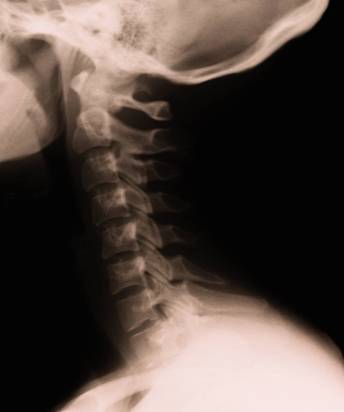

This patient lacks a normal curvature in the cervical spine (neck). This patient suffers from headaches, stress in the shoulders and neck pain from the extra stress on the neck from poor posture.

A: Your poor posture could, over time, be the culprit behind such aches and pains as neck and back pain, tension between the shoulder blades, headaches, tingling/numbness down the arms or legs, muscle spasms, herniated discs pinched nerves and sciatica. Changes in your normal spinal curvatures may also be seen on x-ray when poor posture has been present for extended periods of time.

There are natural curves that should be present in your spine. Your chiropractor will inform you if these are present or if you have an abnormal curve.